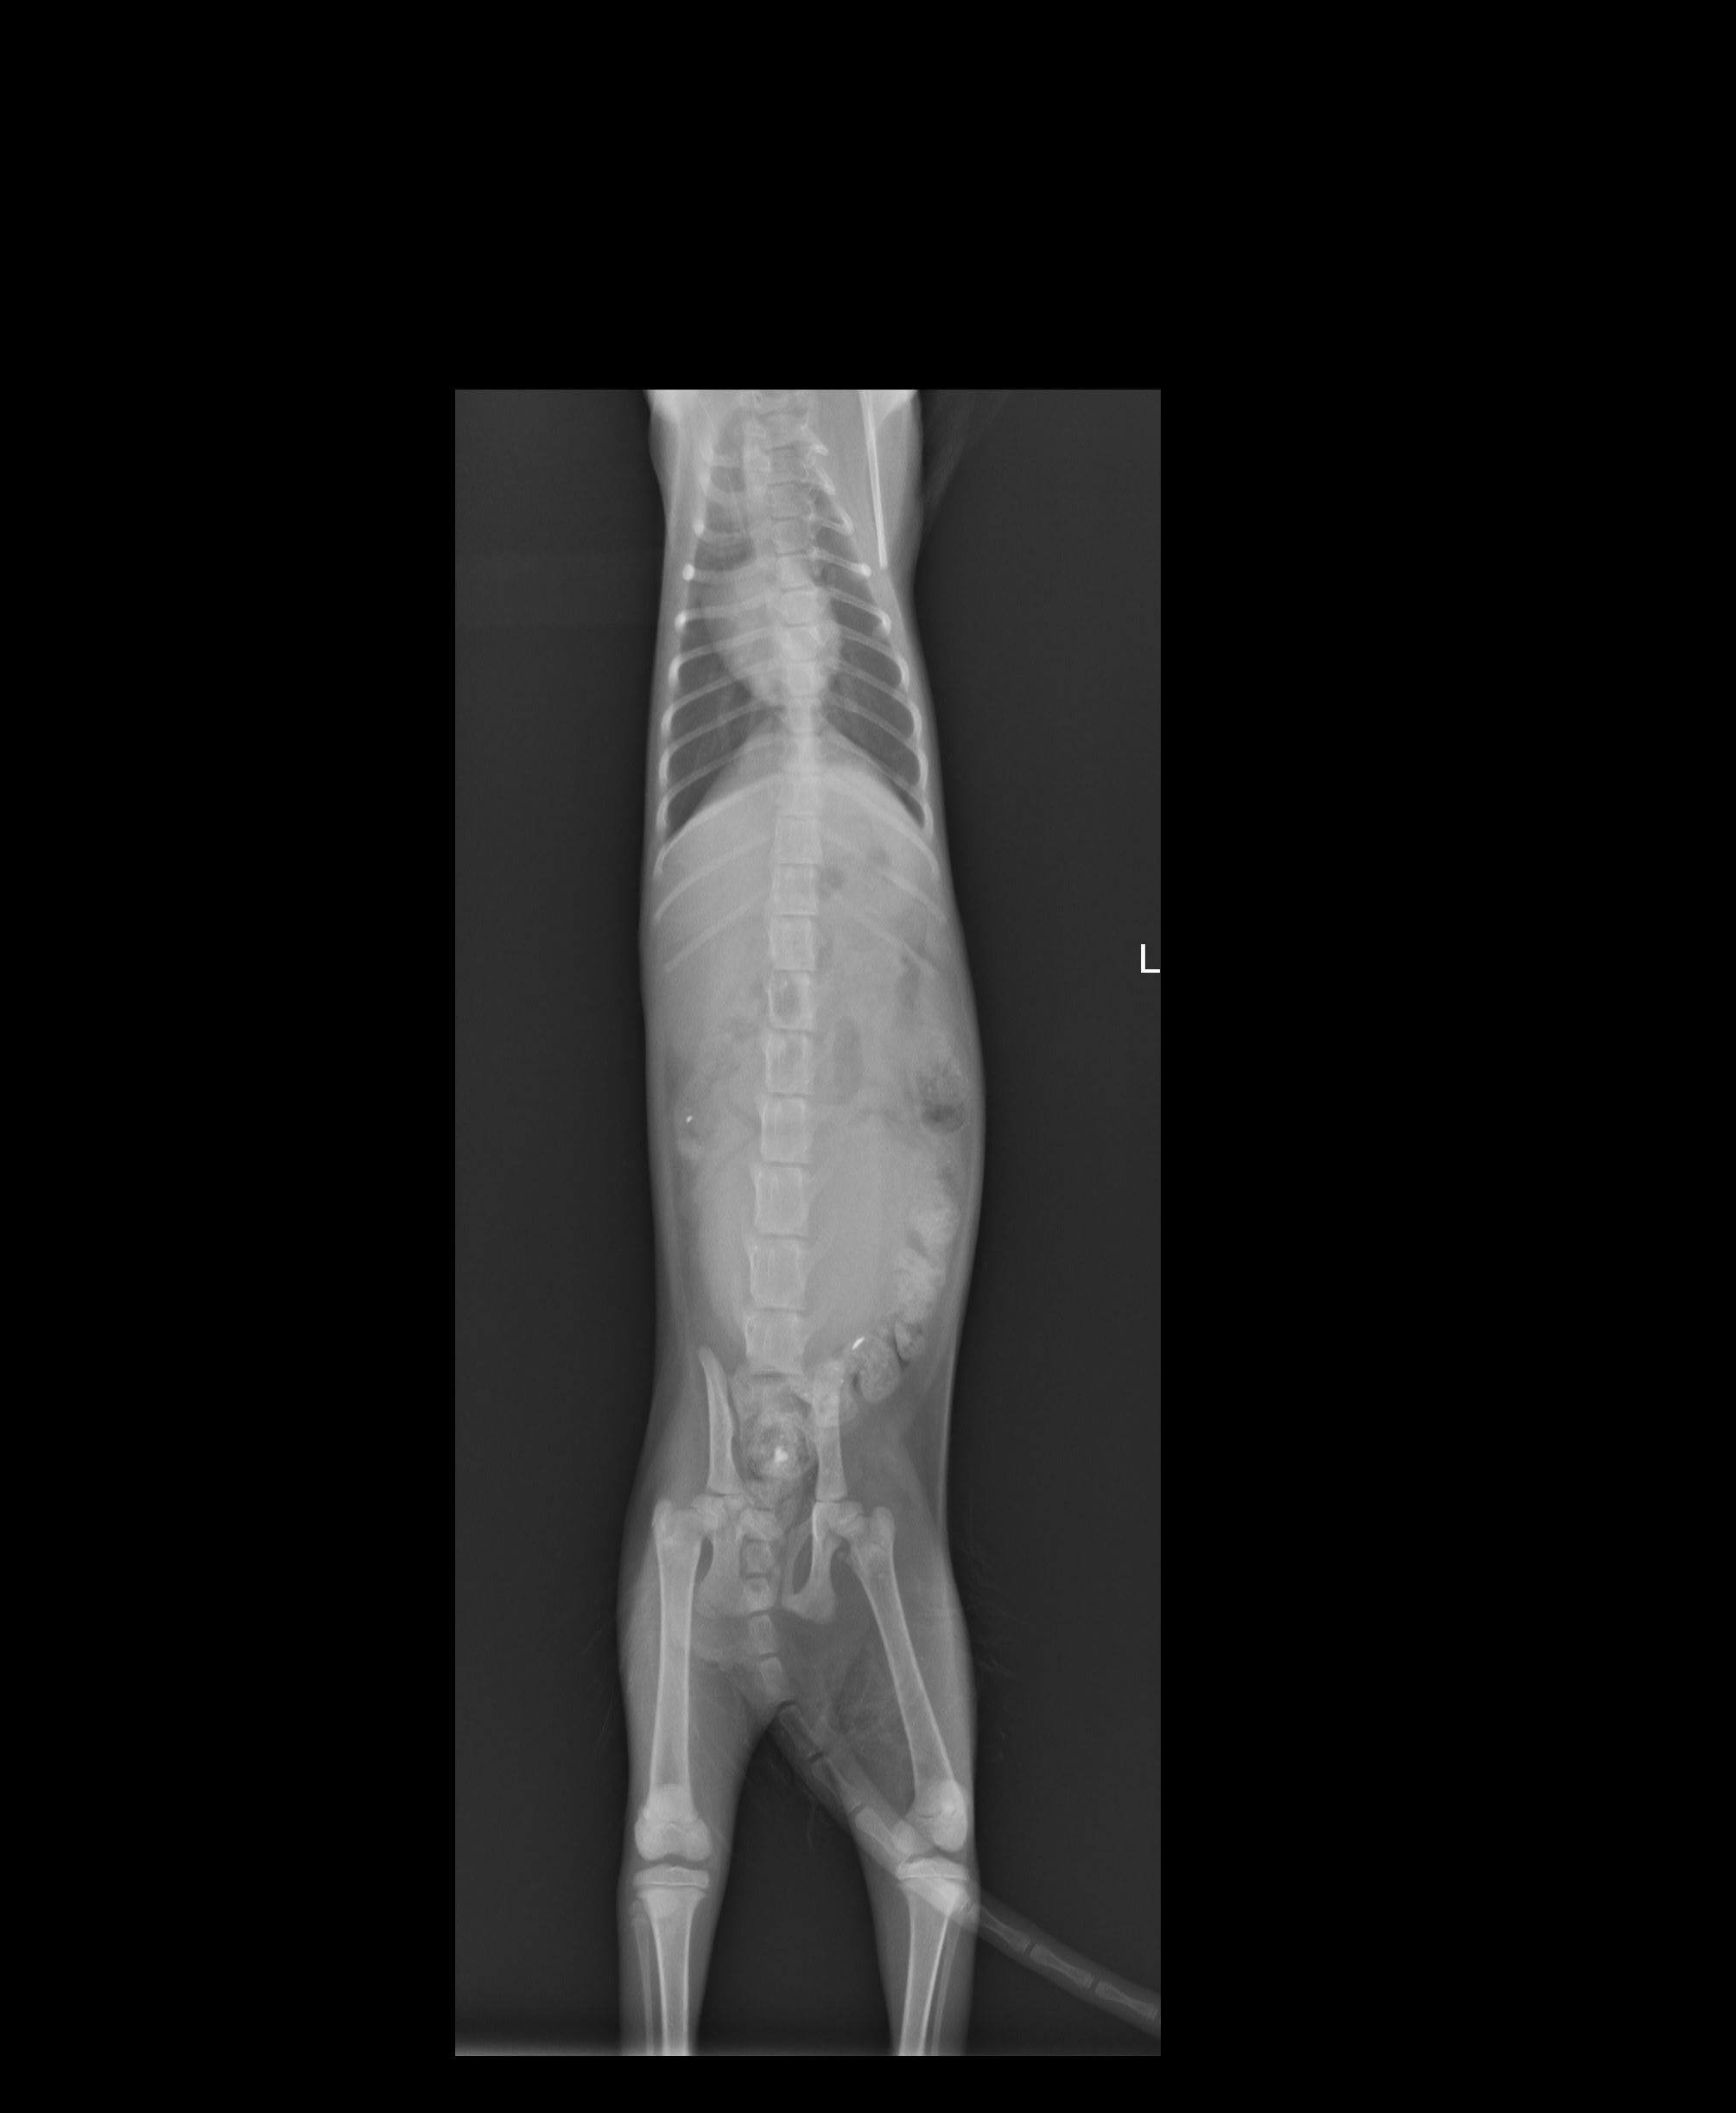

回去傳雞絲頭叩幫手等等集合,到達附近後,兩人開始分頭尋找,這時小幫手即時傳來最新訊息,知道了正確地點,二話不說地直奔,停好車開始尋找,ㄟ∼車底下那隻是…,對照一下資料照,賓果!!是牠了,好小一隻,怎麼是小貓?資料照片看起來像成貓呀?!好心疼,牠好瘦用著兩隻前腳支撐著坐在車底∼先開罐頭測試,很好!不吃∼這時緊張的牠開始想爬進車底裡,哎呀~不行!於是顧不得一切,趕快趴到車底下徒手抓住牠還露在外面的下半身,拉呀拉地抓出了牠,進籠吧!《小朋友你要加油喔》心裡默念著∼動物近況說明: 阿妹牠的X照脊椎沒斷,但就是站不起來,經過幾天治療與觀察,醫生說牠站起來的機率很低,而且後腳有開始萎縮的現象,對於所有疼痛測試皆無反應,而牠也無法自行大小便要人工擠,醫師說之後再試試針灸治療看看,希望針灸有效,牠還那麼小,真不希望是如此的結果發生。阿妹有找到願意照顧她的認養人帶回安置照顧,之後的針灸或其他醫療費用認養人願意自行負擔。